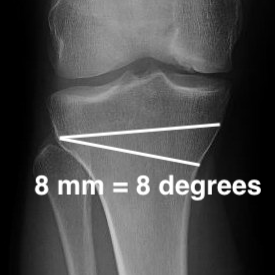

A. Rule of Thumb Method

1mm opening = 1° correction

- i.e. 10o correction, 10 mm open / closing

Based upon average tibial width of 56 mm